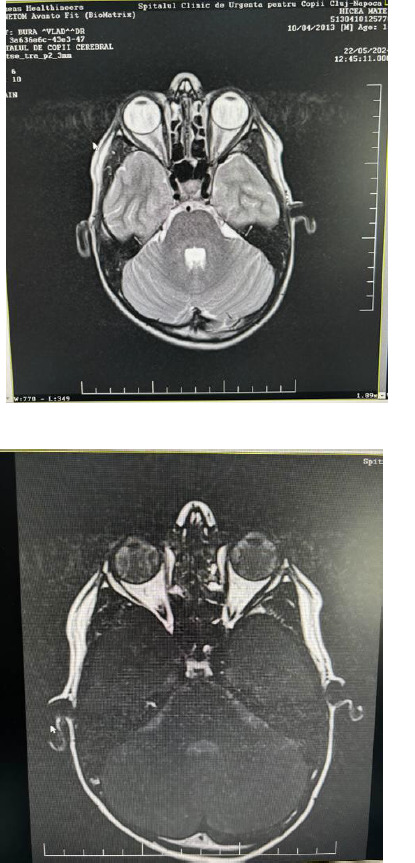

Neuroretinitis is an inflammatory type of optic nerve damage evidenced by the appearance of papillary edema. It also involves inflammation of the retinal layers, as evidenced by the thickening of these layers and the presence of intra- and subretinal fluid. Chorioretinitis is a condition in which inflammation of the posterior component of the uvea, the choroid, leads to further damage to the retina, causing it to become inflamed. The most common causes of neuroretinitis and chorioretinitis in the pediatric population are represented by infectious etiologies. Most cases of neuroretinitis in children are caused by cat scratch disease, which is typically attributed to the bacterium Borrelia burgdorferi. We present the case of a 10-year-old child who presented to our service complaining of a sudden decrease in vision and the appearance of a central scotoma two days before he was referred to our service. Our first diagnosis was of optic neuritis, based on the presence of objective papillary edema on fundus examination. Subsequently, the appearance of chorioretinal foci completely changed the diagnosis and treatment in this case.